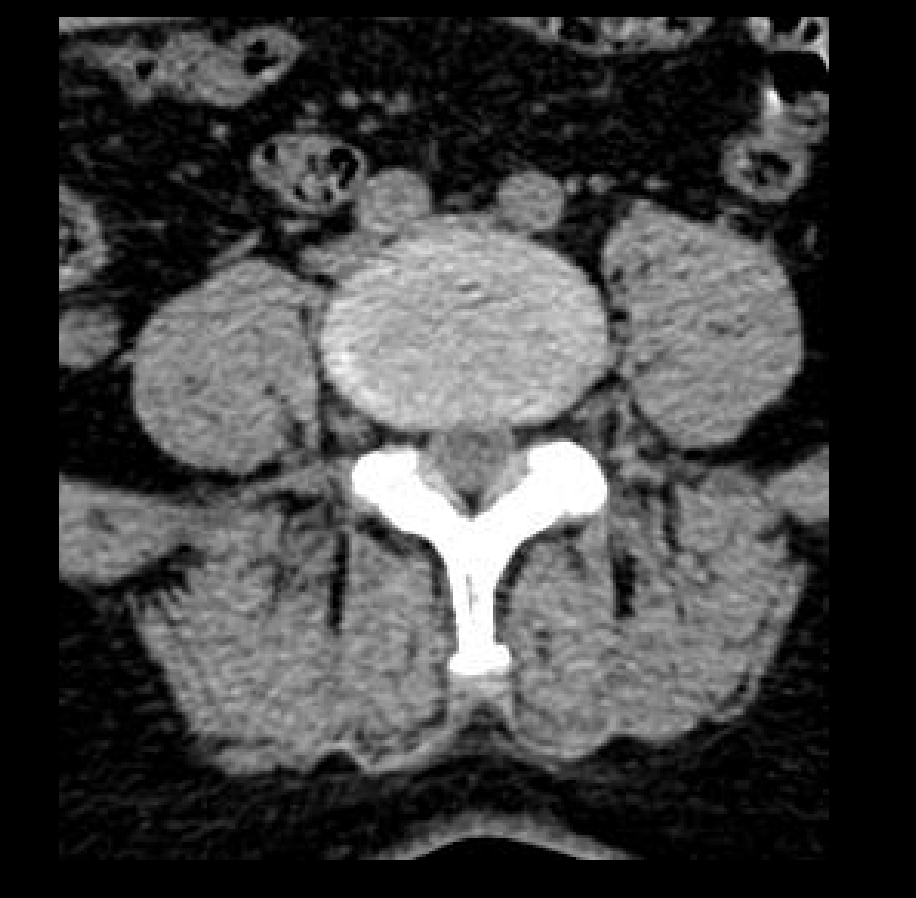

- Giải pháp chẩn đoán hình ảnh mô mềm tiên tiến cho khảo sát ổ bụng

- Tối ưu chất lượng hình ảnh chẩn đoán và giảm phơi nhiễm bức xạ

- Hỗ trợ đánh giá an toàn cho bệnh nhân

- Đảm bảo chất lượng hình ảnh chẩn đoán cao